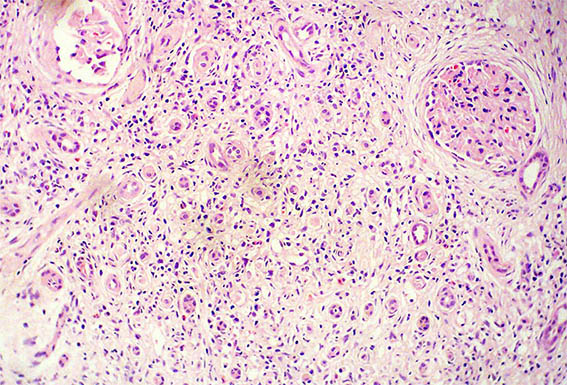

Figura 1. H&E, X100. Note el prominente compromiso tubulointersticial.